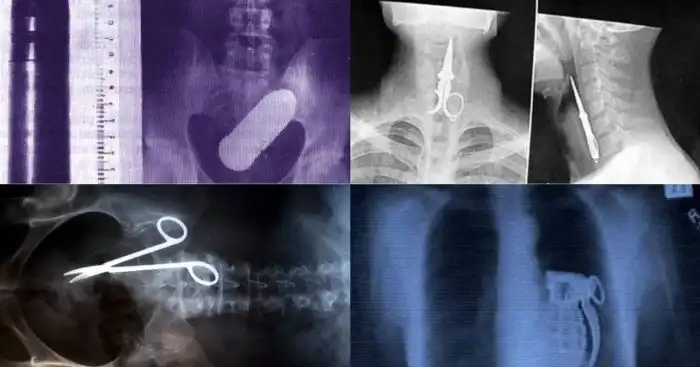

Иногда, кажется, что врачей трудно удивить, ведь за всё время существования этой профессии они повидали немало. Однако стоит взглянуть на рентгеновские снимки и выяснится, что удивляться ещё есть чему.